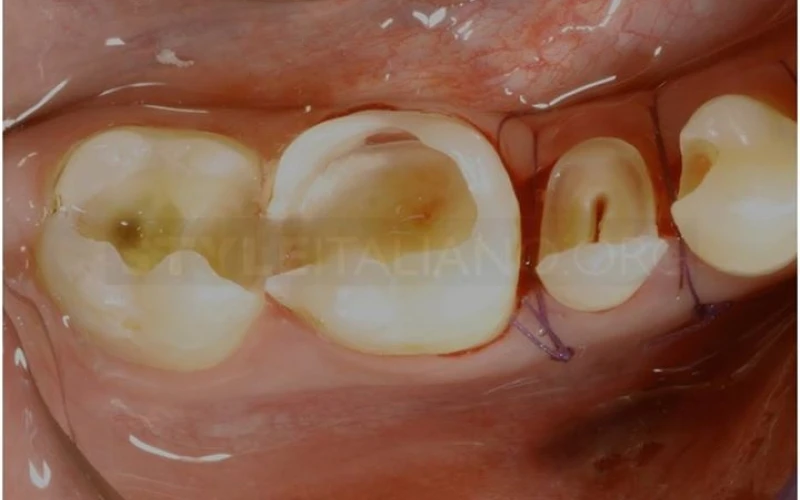

3. Dung dịch phát hiện sâu răng hỗ trợ loại bỏ các mô bệnh.

4. Xoang hàn đã được làm sạch. Đây là thời điểm tốt nhất để lựa chọn kế hoạch điều trị.